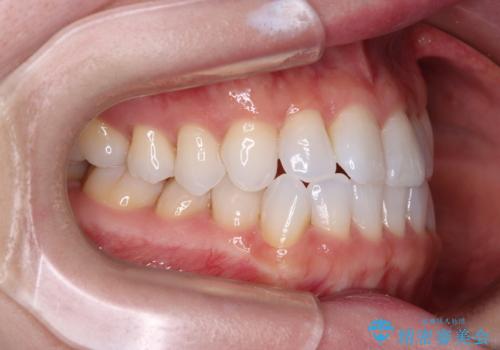

前歯のデコボコをインビザラインで綺麗に

- 上下前歯の叢生を気にして来院された患者様です。

インビザラインでの治療を希望されていて、デコボコの程度が中等度であり、安価なパッケージにて対応可能と判断されたため、インビザライン・モデレートを用いて矯正治療を行うこととしました。